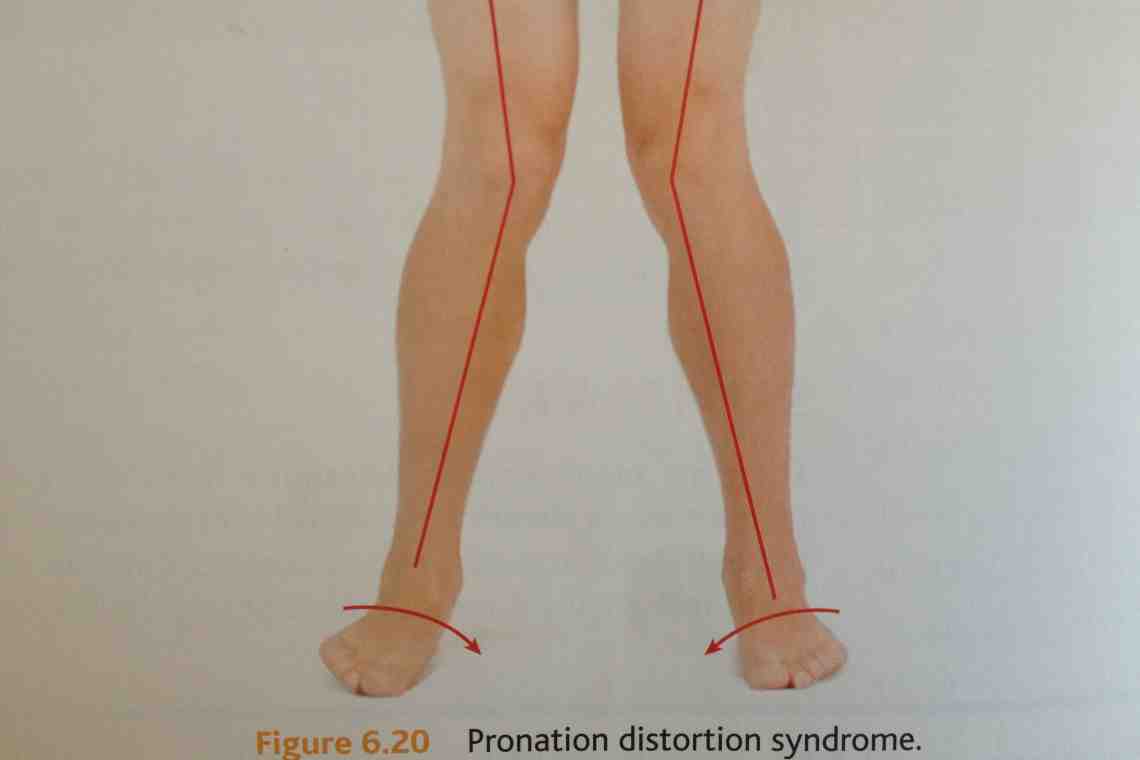

Возможные причины болей в ноге ниже колена и рекомендации